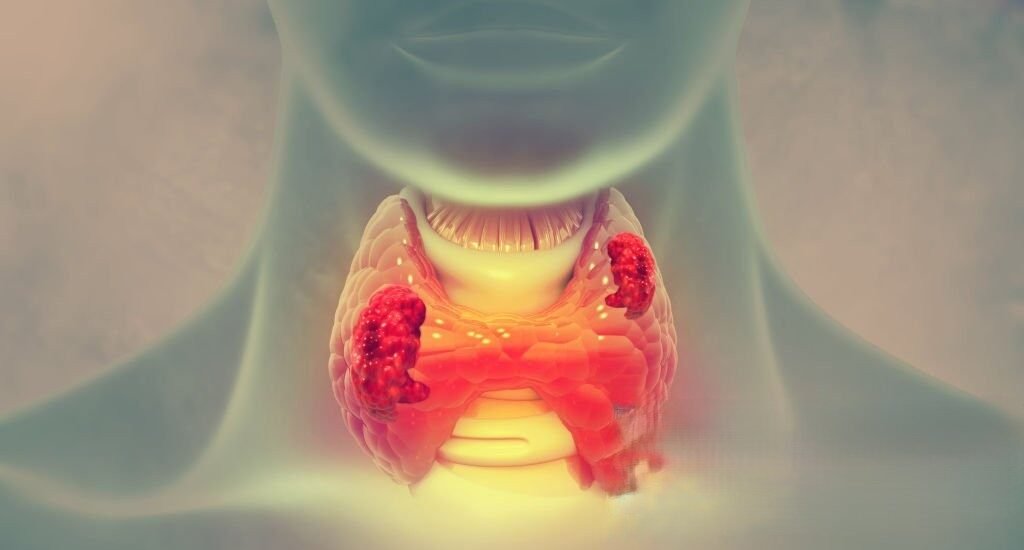

Thyroid Ablation Treatment India: A Complete Guide to Non-Surgical Thyroid Care

Thyroid disorders are becoming increasingly common in today’s fast-paced lifestyle. Among them, thyroid nodules are one of the most frequently diagnosed conditions, often causing

swelling in the neck, discomfort, and anxiety for patients. Traditionally, surgery was considered the primary treatment option. However, with medical advancements, thyroid ablation treatment in India has emerged as a highly effective and minimally invasive alternative. Today, patients looking for safe and advanced solutions are increasingly choosing thyroid ablation treatment in India over conventional surgical methods. This modern approach offers faster recovery, minimal discomfort, and excellent clinical outcomes without the need for major surgery.

Understanding Thyroid Nodules

Thyroid nodules are abnormal growths within the thyroid gland. While most nodules are benign, they can still cause noticeable symptoms such as: